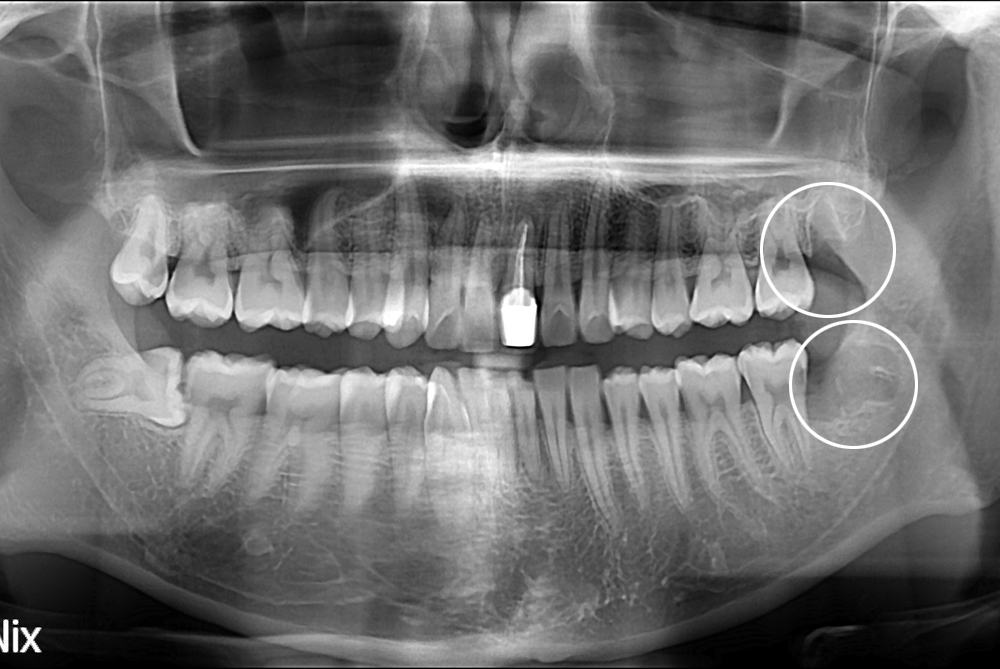

[사랑니] 난발치 사랑니 발치

치료전 : 2017-03-21